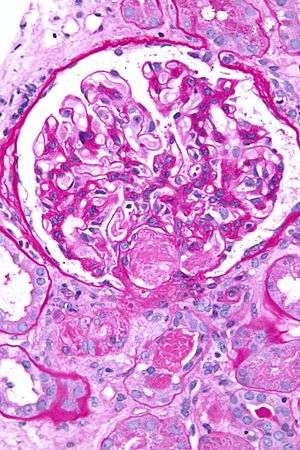

| Micrograph showing an acute thrombotic microangiopathy, the histologic correlate of DIC, in a kidney biopsy. A thrombus is present in the hilum of the glomerulus (center of image). PAS stain. | |